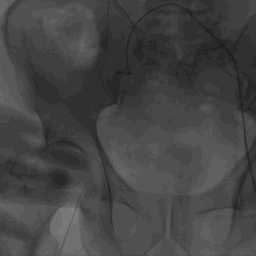

右侧髂外动脉轻度扭曲,双侧股髂动脉血管直径良好

外周血管及主动脉弓解剖

③患者双侧入路血管条件佳,常规选择右侧股动脉为主入路,左侧为辅入路。